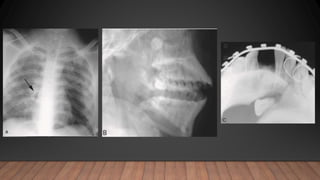

• Radiographic Examination

1. Presence of root fracture

2. Degree of extrusion or intrusion

3. Presence of preexisting periapical disease

4. Extent of root development

5. Size of the pulp chamber and root canal

6. Presence of jaw fractures

7. Tooth fragments and foreign bodies lodged in soft tissues